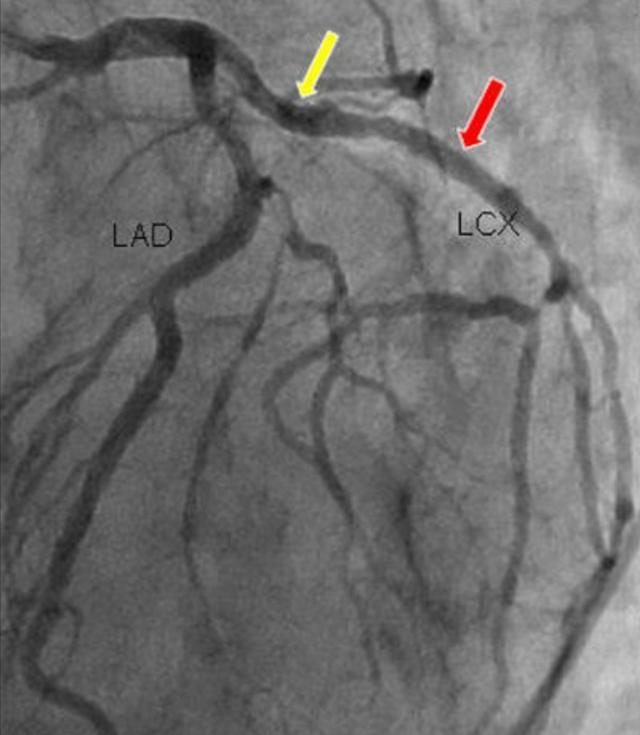

5.冠動脈造影

- 冠動脈造影は検査のために入院が必要で、侵襲的である。

- 冠動脈診断の現在のゴールドスタンダードである、はっきり見えるという利点があり、ある検査で閉塞が非常に深刻であることが判明すれば、再手術の必要なく直接ステントを入れることができる。

- 欠点は、検査費用が高く、入院が必要で、侵襲的であることだ。

でも、その後だ。超音波検査、冠動脈CT、そして特に冠動脈造影検査が行われるようになってから、冠動脈疾患の診断は本当に問題ではなくなりましたこれには、心臓のどの血管がどの程度閉塞しているかを正確に把握することも含まれる。

一般的に、冠動脈疾患が疑われる場合、医師は超音波検査や冠動脈CT検査を受けてもらい、心臓が肥大しているかどうか、心筋症があるかどうか、弁膜症があるかどうかなどを調べます。もちろん、この冠動脈CTは冠動脈疾患のスクリーニングしかできないが、一般的には、冠動脈CTのように問題が見つからなければ、基本的には大きな問題ではない。しかし、もし現時点では、この患者が冠動脈疾患を患っているに違いない、冠動脈造影をしなければならない、とは直接言えない。。

チューブを心臓に通して選択的に撮影することで、血管を見たいところを見ることができ、血管がどの程度詰まっているかもわかります。

したがって、冠動脈造影は冠動脈疾患の診断のためのゴールドスタンダードであり、冠動脈CTはスクリーニング検査に過ぎないことを忘れてはならない。

6.冠動脈造影冠動脈造影は侵襲的な検査であり、現在でも冠動脈疾患診断の "ゴールドスタンダード "である。.狭窄病変の位置を特定し,その範囲を推定することができる。内腔径が70~75%以上縮小すると血液供給に重大な影響を及ぼすことが一般に認められている。

冠動脈CTは冠動脈狭窄の有無と程度を検出できる非侵襲的検査であり、冠動脈造影は冠動脈疾患診断のゴールドスタンダードである。